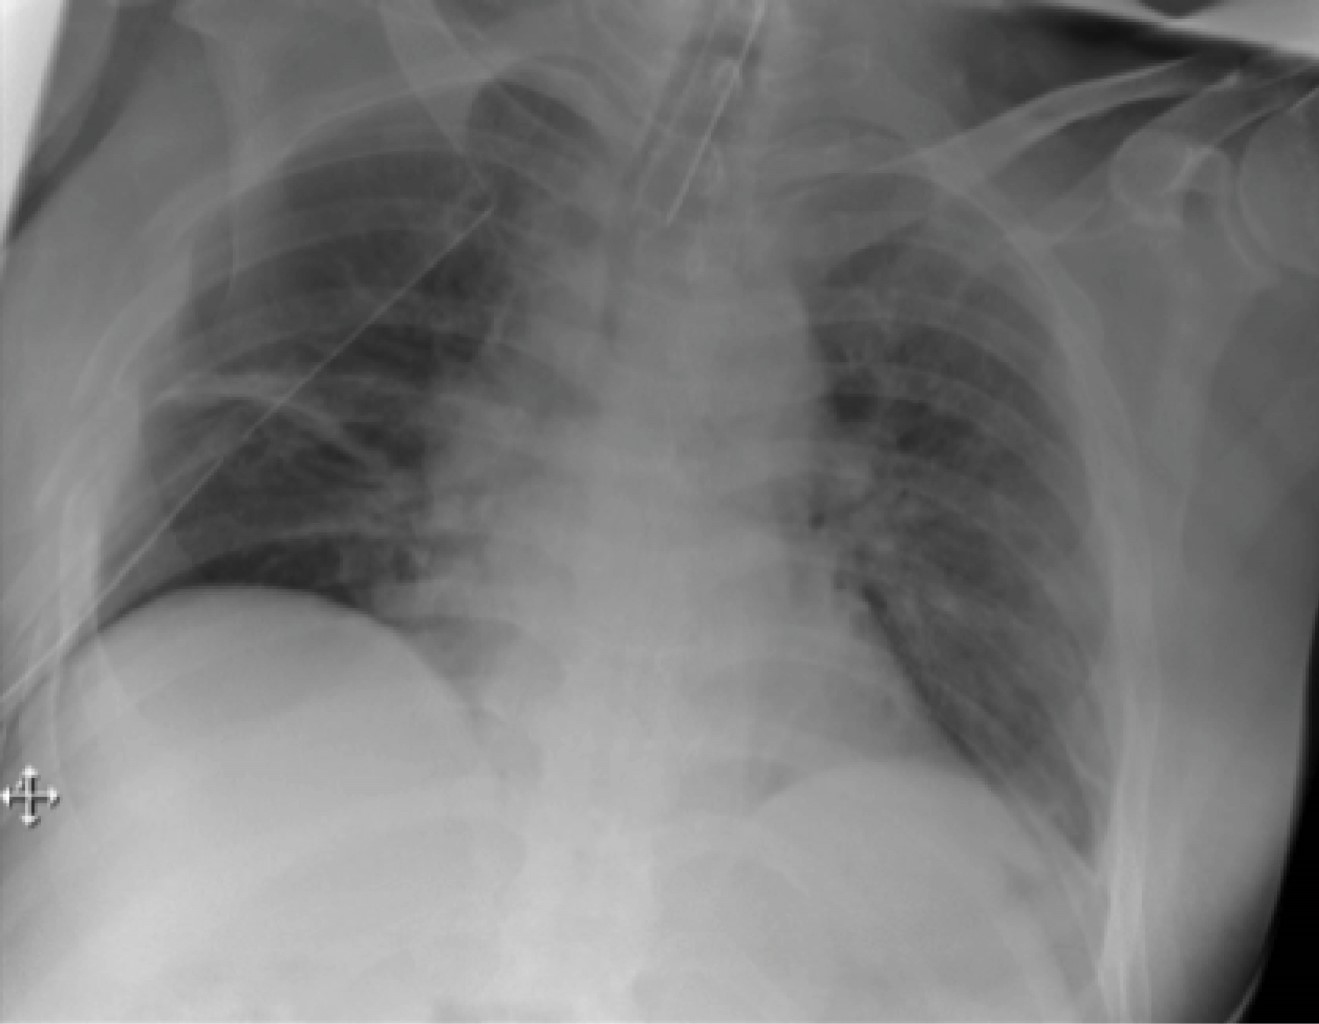

Estudios de laboratorio normales, exceptuando leucocitos: 14.2 mil/mm³, CPK 2,948 μmol/L. Se realiza radiografía de tórax (Figura 1) y tomografía computarizada (TC) toraco-abdominal (Figura 2, 3 y 4) observando neumotórax derecho de 30%, fracturas costales bilaterales de segunda a la séptima. En ambos estudios no se evidencia la presencia de hernia diafragmática.

En el paciente traumatizado que se encuentra estable, la TC con contraste intravenoso es el estudio de referencia para el diagnóstico y planeación quirúrgica, con una sensibilidad de 14-71% y especificidad de 76-99%2, y aumenta si se utiliza la TC helicoidal con reconstrucción en 3D (sensibilidad 82-87%, especificidad 72-99%).8 Magu y colaboradores reportan una sensibilidad similar a la radiografía de tórax hasta en 50%.5 Los datos tomográficos más sugestivos se muestran en la Tabla 1.2,8

Figura 2